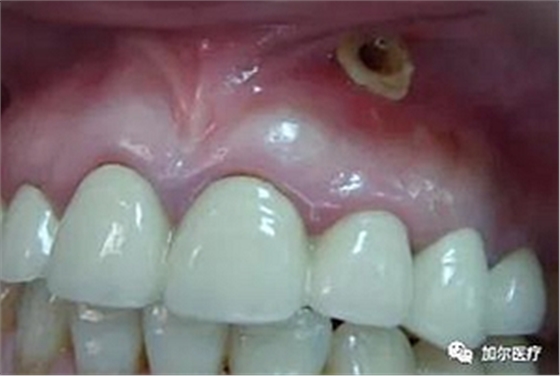

最近牙齦起膿包,總會有白色膿液流出,但不會痛,牙醫(yī)檢查出是根尖周炎,后面也做了排膿還消炎上藥,關鍵是做完根管治療膿包又長回來,奇怪的是,既然還會長膿包,那為什么要做根管治療?

說明根管治療中殘髓清除不徹底所致,實際上就是根管失敗了,正常的根管治療可以清理掉根尖內病變的牙髓,根管消毒后把髓腔充填密封,但是牙膠尖不能超充,這樣你才不會再起膿包,不過根管前得先排膿再消炎上藥,一般感染物質除去后,沒

有及時根管治療的話,瘺管口會自動關閉,感染性物質還會卷土重來長出膿包。